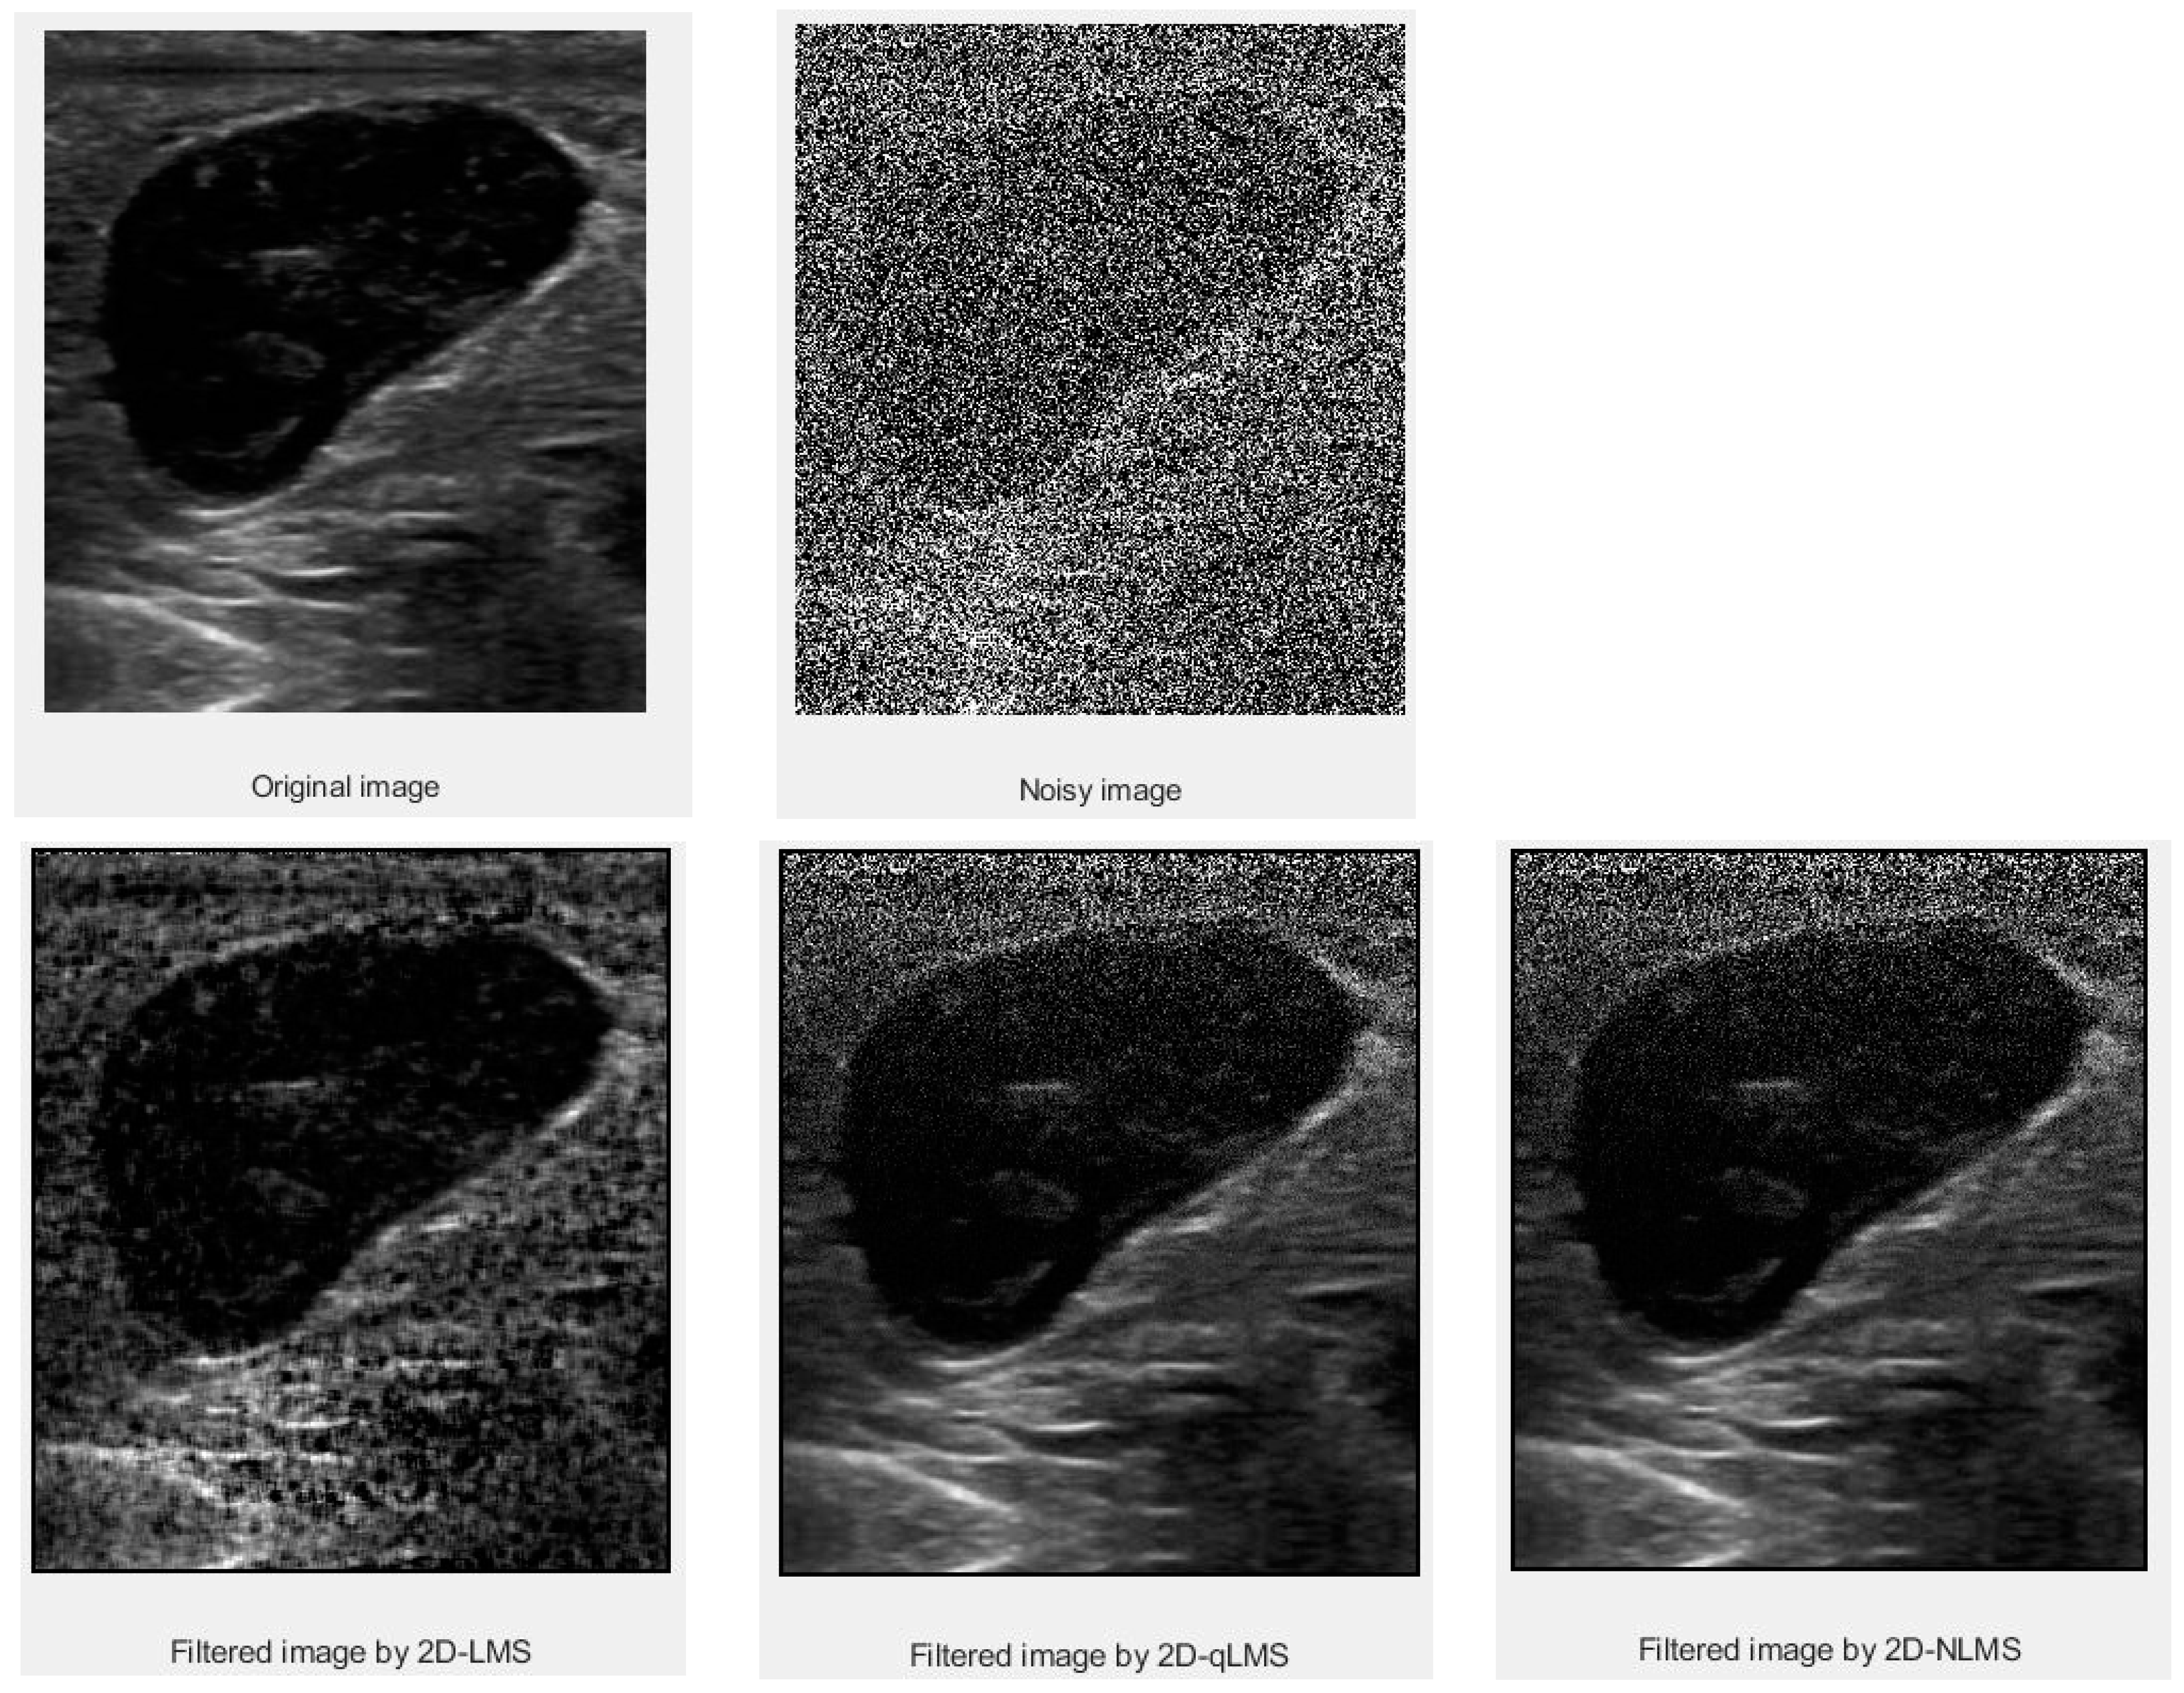

3. Results and Discussion

3.1. PSNR Values

3.2. SSIM Values

| Data | Filter Size | LMS | QLMS | NLMS |

|---|---|---|---|---|

| Thyroid | 5 × 5 | 64.0167 | 70.0593 | 72.8341 |

| Thyroid Cyst | 5 × 5 | 64.0506 | 69.1289 | 72.8708 |

| Mass in Muscle | 5 × 5 | 63.8117 | 69.1211 | 72.2958 |

| Data | Filter Size | LMS | QLMS | NLMS |

|---|---|---|---|---|

| Thyroid | 5 × 5 | 0.9996 | 0.9997 | 0.9998 |

| Thyroid Cyst | 5 × 5 | 0.9993 | 0.9997 | 0.9999 |

| Mass in Muscle | 5 × 5 | 0.9996 | 0.9998 | 0.9999 |